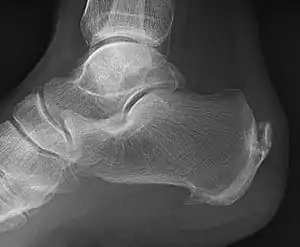

![]() | |

| A radiograph showing osteophytes on the posterior and inferior aspects of the calcaneus | |